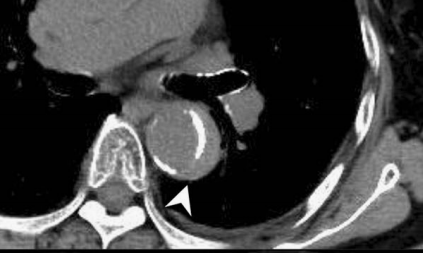

下图的胸部CT平扫,有什么致命的问题?

仔细一看,主动脉里面有线样阴影!并且,线样阴影两边的密度一高一低!

增强CT一看,主动脉夹层,密度相对高的是流动的血液!